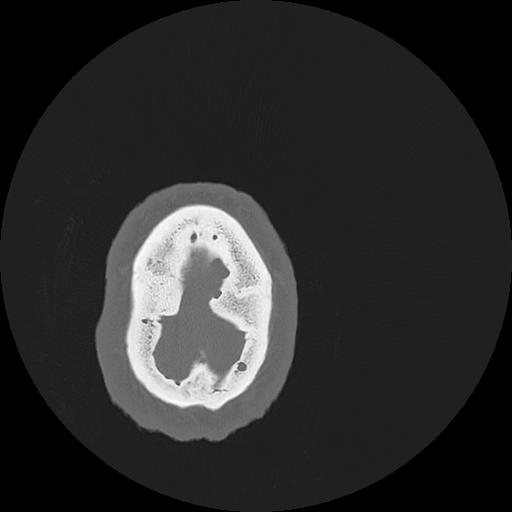

7 HUESO,,Vol,0.5,HUESO,,